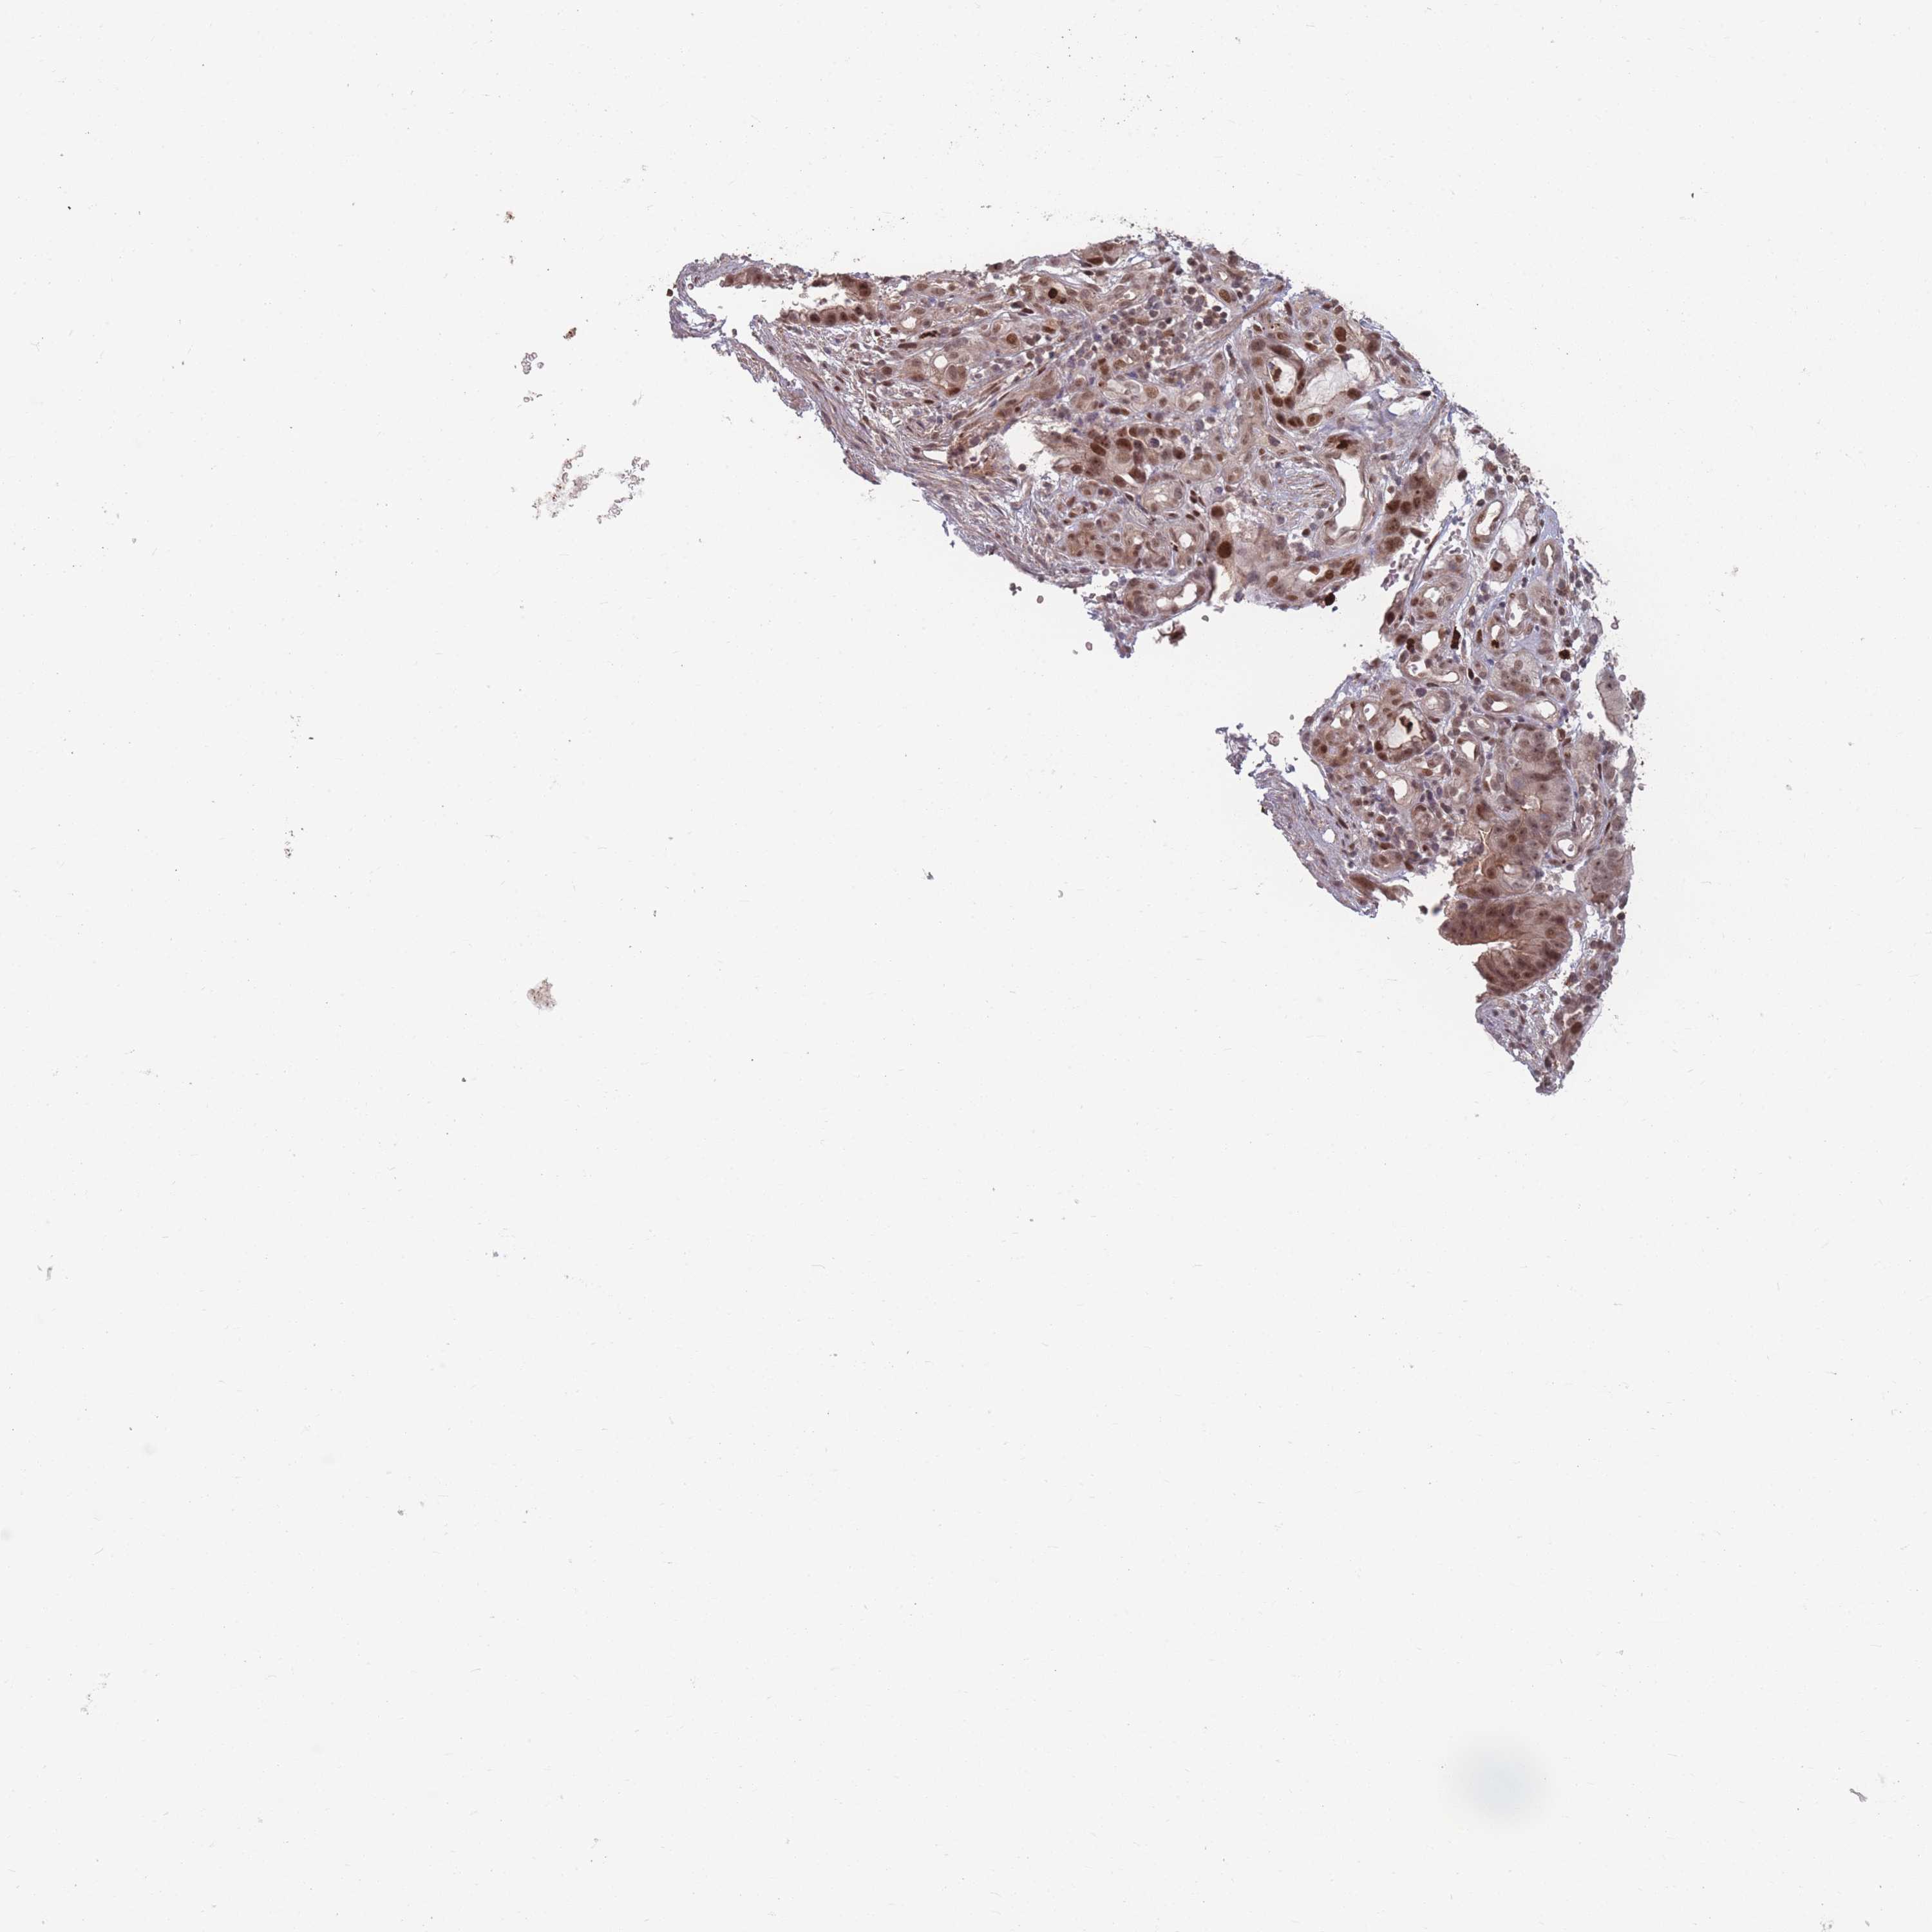

STOMACH CANCER - Protein expressioni

A mouse-over function shows sample information and annotation data. Click on an image to view it in a full screen mode. Samples can be filtered based on level of antibody staining by selecting one or several of the following categories: high, medium, low and not detected. The assay and annotation is described here.

Note that samples used for immunohistochemistry by the Human Protein Atlas do not correspond to samples in the TCGA dataset.

Antibody stainingi

Antibody staining in the annotated cell types in the current human tissue is reported as not detected, low, medium, or high, based on conventional immunohistochemistry profiling in selected tissues. This score is based on the combination of the staining intensity and fraction of stained cells.

Each image is clickable and will lead to virtual microscopy that enables deeper exploration of all samples and also displays staining intensity scores, fraction scores and subcellular localization as well as patient and tissue information for each sample.

Antibody HPA043470

Antibody HPA048143

Staining

High

Medium

Low

Not detected

Intensity

Strong

Moderate

Weak

Negative

Quantity

>75%

75%-25%

<25%

None

Location

Nuclear

Cytoplasmic/membranous

Cytoplasmic/membranous,nuclear

Adenocarcinoma, NOS